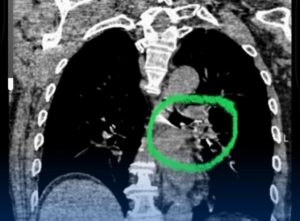

У пациента диагностировано инородное тело в левом главном бронхе — кусочек яблока размером 2,0х1,5 см, полностью перекрывавший дыхательные пути. Ситуацию значительно осложняли сопутствующие заболевания: последствия перенесенного острого нарушения мозгового кровообращения (1995 г.), дизартрия, левосторонний гемипарез, а также артериальная гипертензия III степени (ФК 4).

В условиях операционной ЦРБ г. Конаев специалистом проведено удаление инородного тела с помощью аппарата видеобронхоскопа под интубационным наркозом. Благодаря своевременным и профессиональным действиям врача дыхательные пути пациента были полностью восстановлены, что позволило избежать тяжёлых осложнений и угрозы жизни.